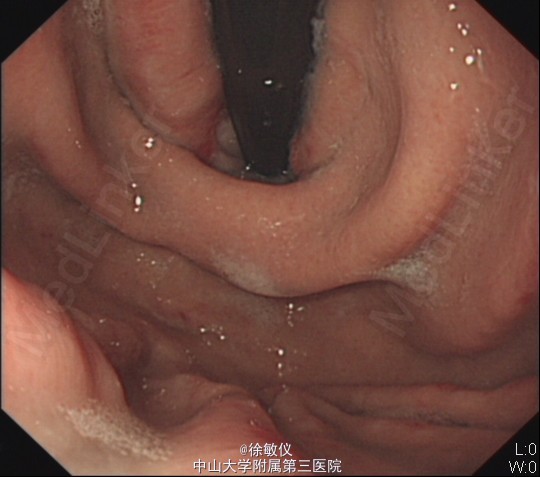

入院后予抗病毒、护肝、降门脉压、抑酸护胃、升白、营养支持等治疗。并于2015-5-13行胃镜检查,并行食管静脉曲张套扎术,结果回报:1.食管重度静脉曲张(Li+Lm,F3,CB,RC+)并套扎术;2.胃底重度静脉曲张(Lg-C,F3,CB,RC+);3.门脉高压性胃病。予请肝脏外科医师会诊,建议择期行脾切除手术。 诊断:乙型肝炎后肝硬化失代偿期 食管静脉曲张(重度,套扎术后) 重度胃底静脉曲张 门脉高压性胃肠病 脾功能亢进